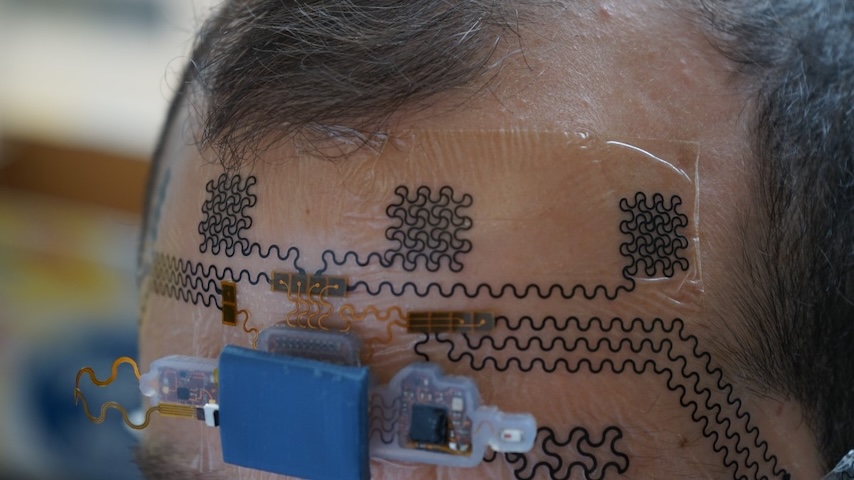

More Ultrasound Tech: Wearable Patch Reads Muscle Activity Remotely

Most people are familiar with ultrasound as an imaging modality. A transducer produces high frequency sound waves that bounce off different parts of the body. When the waves echo back to a receiver, you can generate electrical signals to visualize organs or other tissues. Those sound waves, however, can be used in a different way. By using ultrasound to activate “robocilia,” or manmade cilia on a stent, a process called acoustic streaming could help loosen encrustation in a non-invasive manner.